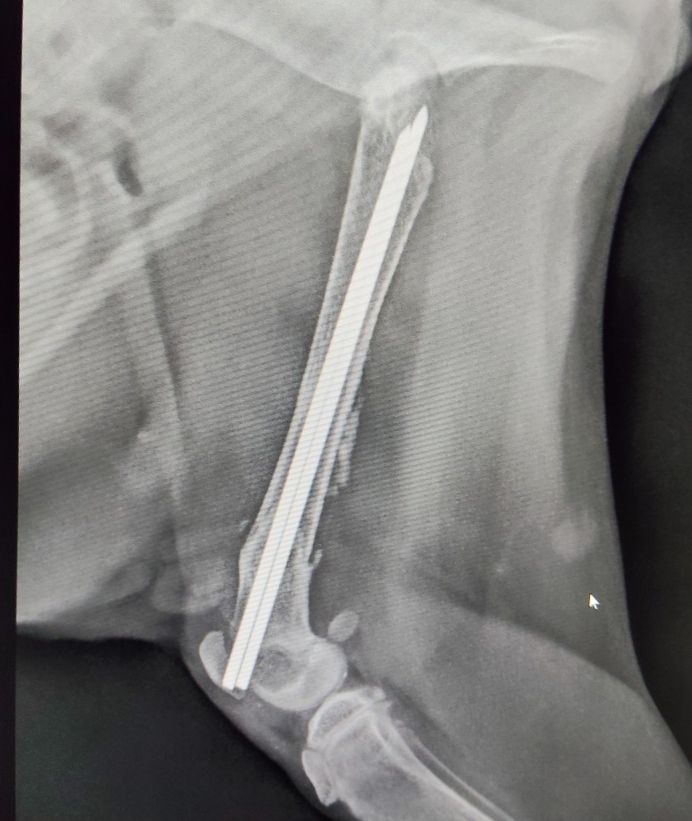

| Krankheiten / Handicaps | Erfolgreiche O.P. nach Oberschenkelbruch |

Beschreibung | Auch Cherry wurde Opfer eines Autounfalls. Natürlich ließ man auch sie einfach liegen und fuhr weiter. Aber sie hatte Glück, der nachfolgende Autofahrer hielt an und brachte sie schnell zum Tierarzt. Die kleine Katzendame hatte einen Bruch am rechten Oberschenkel. Sie wurde operiert und der Bruch wurde mit Stiften fixiert. Inzwischen ist alles gut verheilt und die Stifte auch schon wieder entfernt. Sie hat keine bleibenden Schäden und kann springen und rennen. Nicht mal ein Humpeln ist zurückgeblieben. Nach der O.P. war Cherry sehr unglücklich und traurig im Tierheim. So nahm Silvia auch sie mit nach Hause und sie teilte sich das Gartenhäuschen mit Anita, Aylin, Pantero, Pulgita, Ozzy und Rosa (wir stellen sie separat vor). Cherry ist eine ganz entzückende Katze. Super süß und lieb. Sie schaut gerne aus dem Fenster und hätte zu gerne Freigang. Sie ist neugierig und verspielt, aber nicht zu sehr aktiv. Sie genießt es, mit den anderen Katzenkindern zusammen zu sein und kuschelt gerne mit ihnen im Körbchen. Sie ist devot, sehr friedliebend und hat ein überaus freundliches Wesen. Sie ist eine sehr liebevolle Katze. Cherry vermisst die menschliche Zuneigung. Sie ist ein sehr verschmustes Kätzchen, welches die Kuschel – und Schmuseeinheiten des Menschen braucht. Für Cherry suchen wir ein Zuhause, wo sie für immer bleiben darf und wo man sie lieb hat und man sich mit ihr beschäftigt. Wo sie ihre Schmuse – und Kuscheleinheiten bekommt und wo sie im Bett schlafen darf und ein festes Familienmitglied ist. Das Tierheim ist wieder proppenvoll und so lebt sie derzeit zusammen mit Rosa, Anita und Aylin, Pulgita, Pantero und Ozzy (wir stellen sie alle separat vor. ) bei Silvia auf dem Gelände im Gartenhäuschen. Allerdings ist das nur eine Notlösung. Silvia fehlt einfach die Zeit, um den vier Mädels im Gartenhäuschen ausreichend Schmuseeinheiten zukommen zu lassen. Sie hat 11 Katzen und 2 Hunde bei sich in Pflege. ——————————————————————————- Wir suchen wirklich sehr dringend eine liebe Familie. Auch sie hat in ihrem kleinen Leben bereits genug erlebt. Daher suchen wir für sie eine Endstelle. Eine liebe Familie, wo verschmuste und verspielte Katzenkinder willkommen sind. Bitte bedenken Sie, dass kleine Katzenkinder nicht nebenher laufen. Sie brauchen Zuneigung, Aufmerksamkeit und Betreuung. Man muss ihnen zeigen, dass sie Vertrauen haben und sich sicher fühlen können. Und da darf das Spielen und Schmusen nicht zu kurz kommen. Dafür sollte man ausreichend Zeit aufbringen können. Mit den anderen Katzen versteht sie sich sehr gut und daher kann sie gerne auch zu gleichaltrigen Katzen, die bereits in der Familie leben, hinzu vermittelt werden. Auch mit Hunden kommt sie gut klar. Liebe Kinder sind herzlich willkommen. Sollte noch kein Katzenmädel in Cherrys Alter in der Familie leben, vermitteln wir sie gerne mit einer Freundin aus ihrer jetzigen Gruppe. Z.B. Rosa. Auf keinen Fall wird sie als Einzelkatze oder reine Wohnungskatze vermittelt. Cherry soll Freigang in katzensicherer Umgebung bekommen. Es soll auch ein Haushalt sein, wo eine Katzenklappe vorhanden ist oder noch installiert wird. Cherry wird FIV und Leukose getestet, Tollwut, Schnupfen, Seuche und Leukose geimpft, entwurmt, gechipt und kastriert abgegeben. Seit 29.04. ist Cherry nun auf Pflegeplatz bei Hella in Oststeinbek bei Hamburg. Wer Interesse an Cherry hat, kann sie gerne besuchen kommen. Cherry darf für immer bei ihrer Pflegestelle bleiben 🙂 |